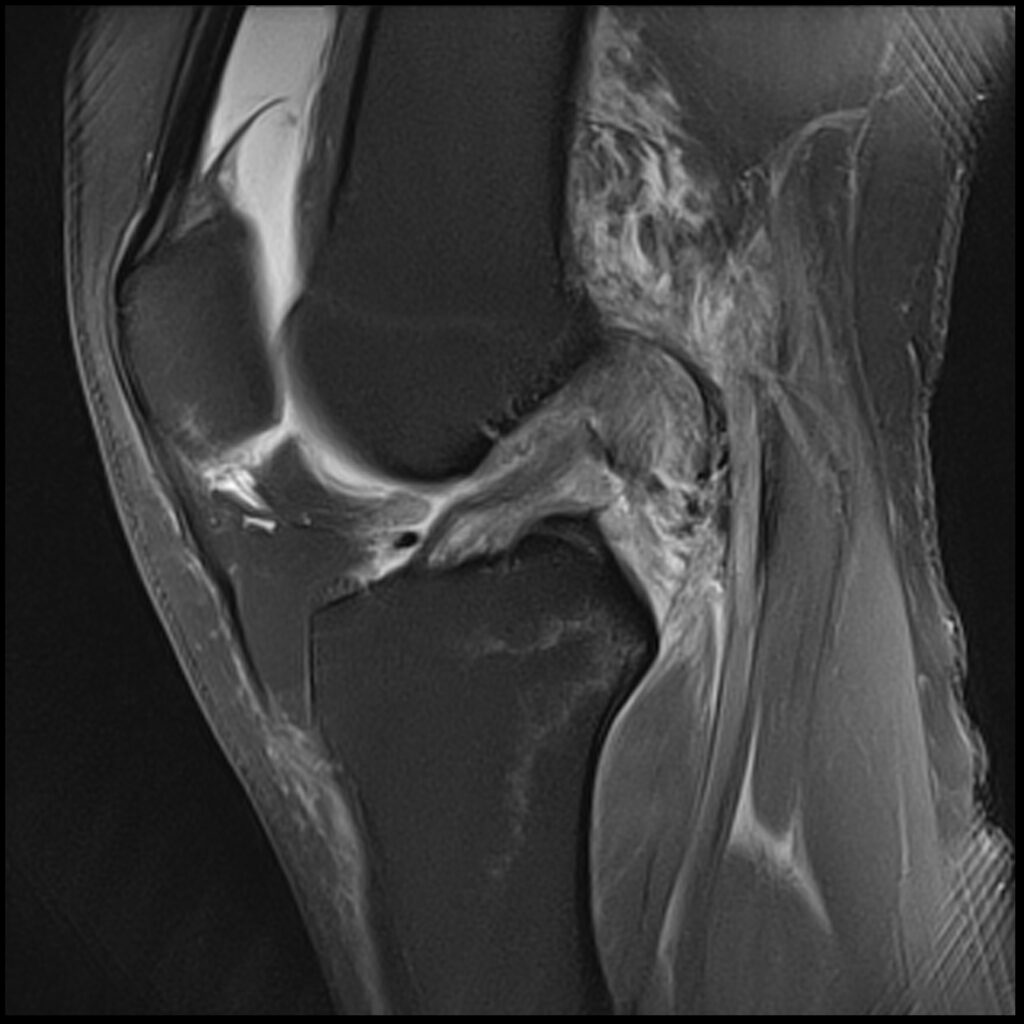

Patient D, age 19, sustained a competitive tumbling injury that involved a hard landing with the pathognomonic plant and pivot that directly tractions the ACL along its doubly obliqued path. The first MR scan was done the day after the trauma. She was initially treated 5 days post-injury. Her knee effusion was completely aspirated, then replaced with 3cc of autologous platelet-rich plasma and 5cc of platelet-poor plasma. Using ultrasound guidance, the ACL origin at the posterior femur was treated after carefully avoiding the vasculature and nerves. She was then instructed not to bear weight for 3 days, then use crutches/assisted weight bearing for 2 weeks. She was then to use a compression knee sleeve during sports or exercise. At her follow-up visit at 4 weeks, she was still having some instability at times and lateral knee pain. Her knee was evaluated with an ultrasound, and any areas of pathology seen were treated with hypertonic dextrose injection and needling technique. This included her medial and lateral collateral ligaments, and the patellar tendon and ligament. At 12-week follow-up, she continued to have some minor issues with her knee, so another evaluation and treatment were performed with hypertonic dextrose to the injured ligament and tendon areas found on the ultrasound examination. We obtained a new MR for her 16-week follow-up and noticed the ACL had re-ligamentized, and she reported full function and return to exercise. At 5-year follow-up, she claimed she was fully active, pain-free, but no longer tumbling.

Patient D Before

Patient D After